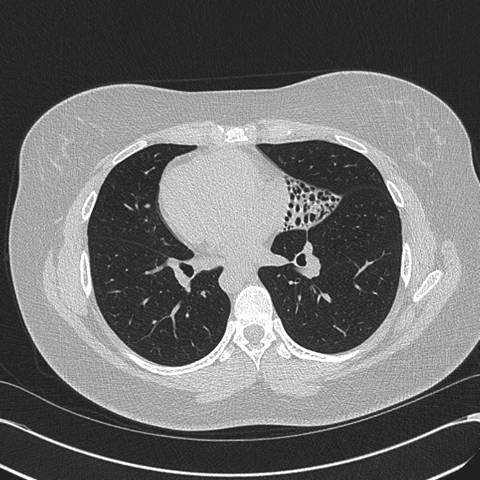

Figure 2: High resolution computed tomography (CT) of the Chest —demonstrates situs inversus totalis and volume loss of the "left middle lobe" with bronchiectasis, presumably fibrotic.